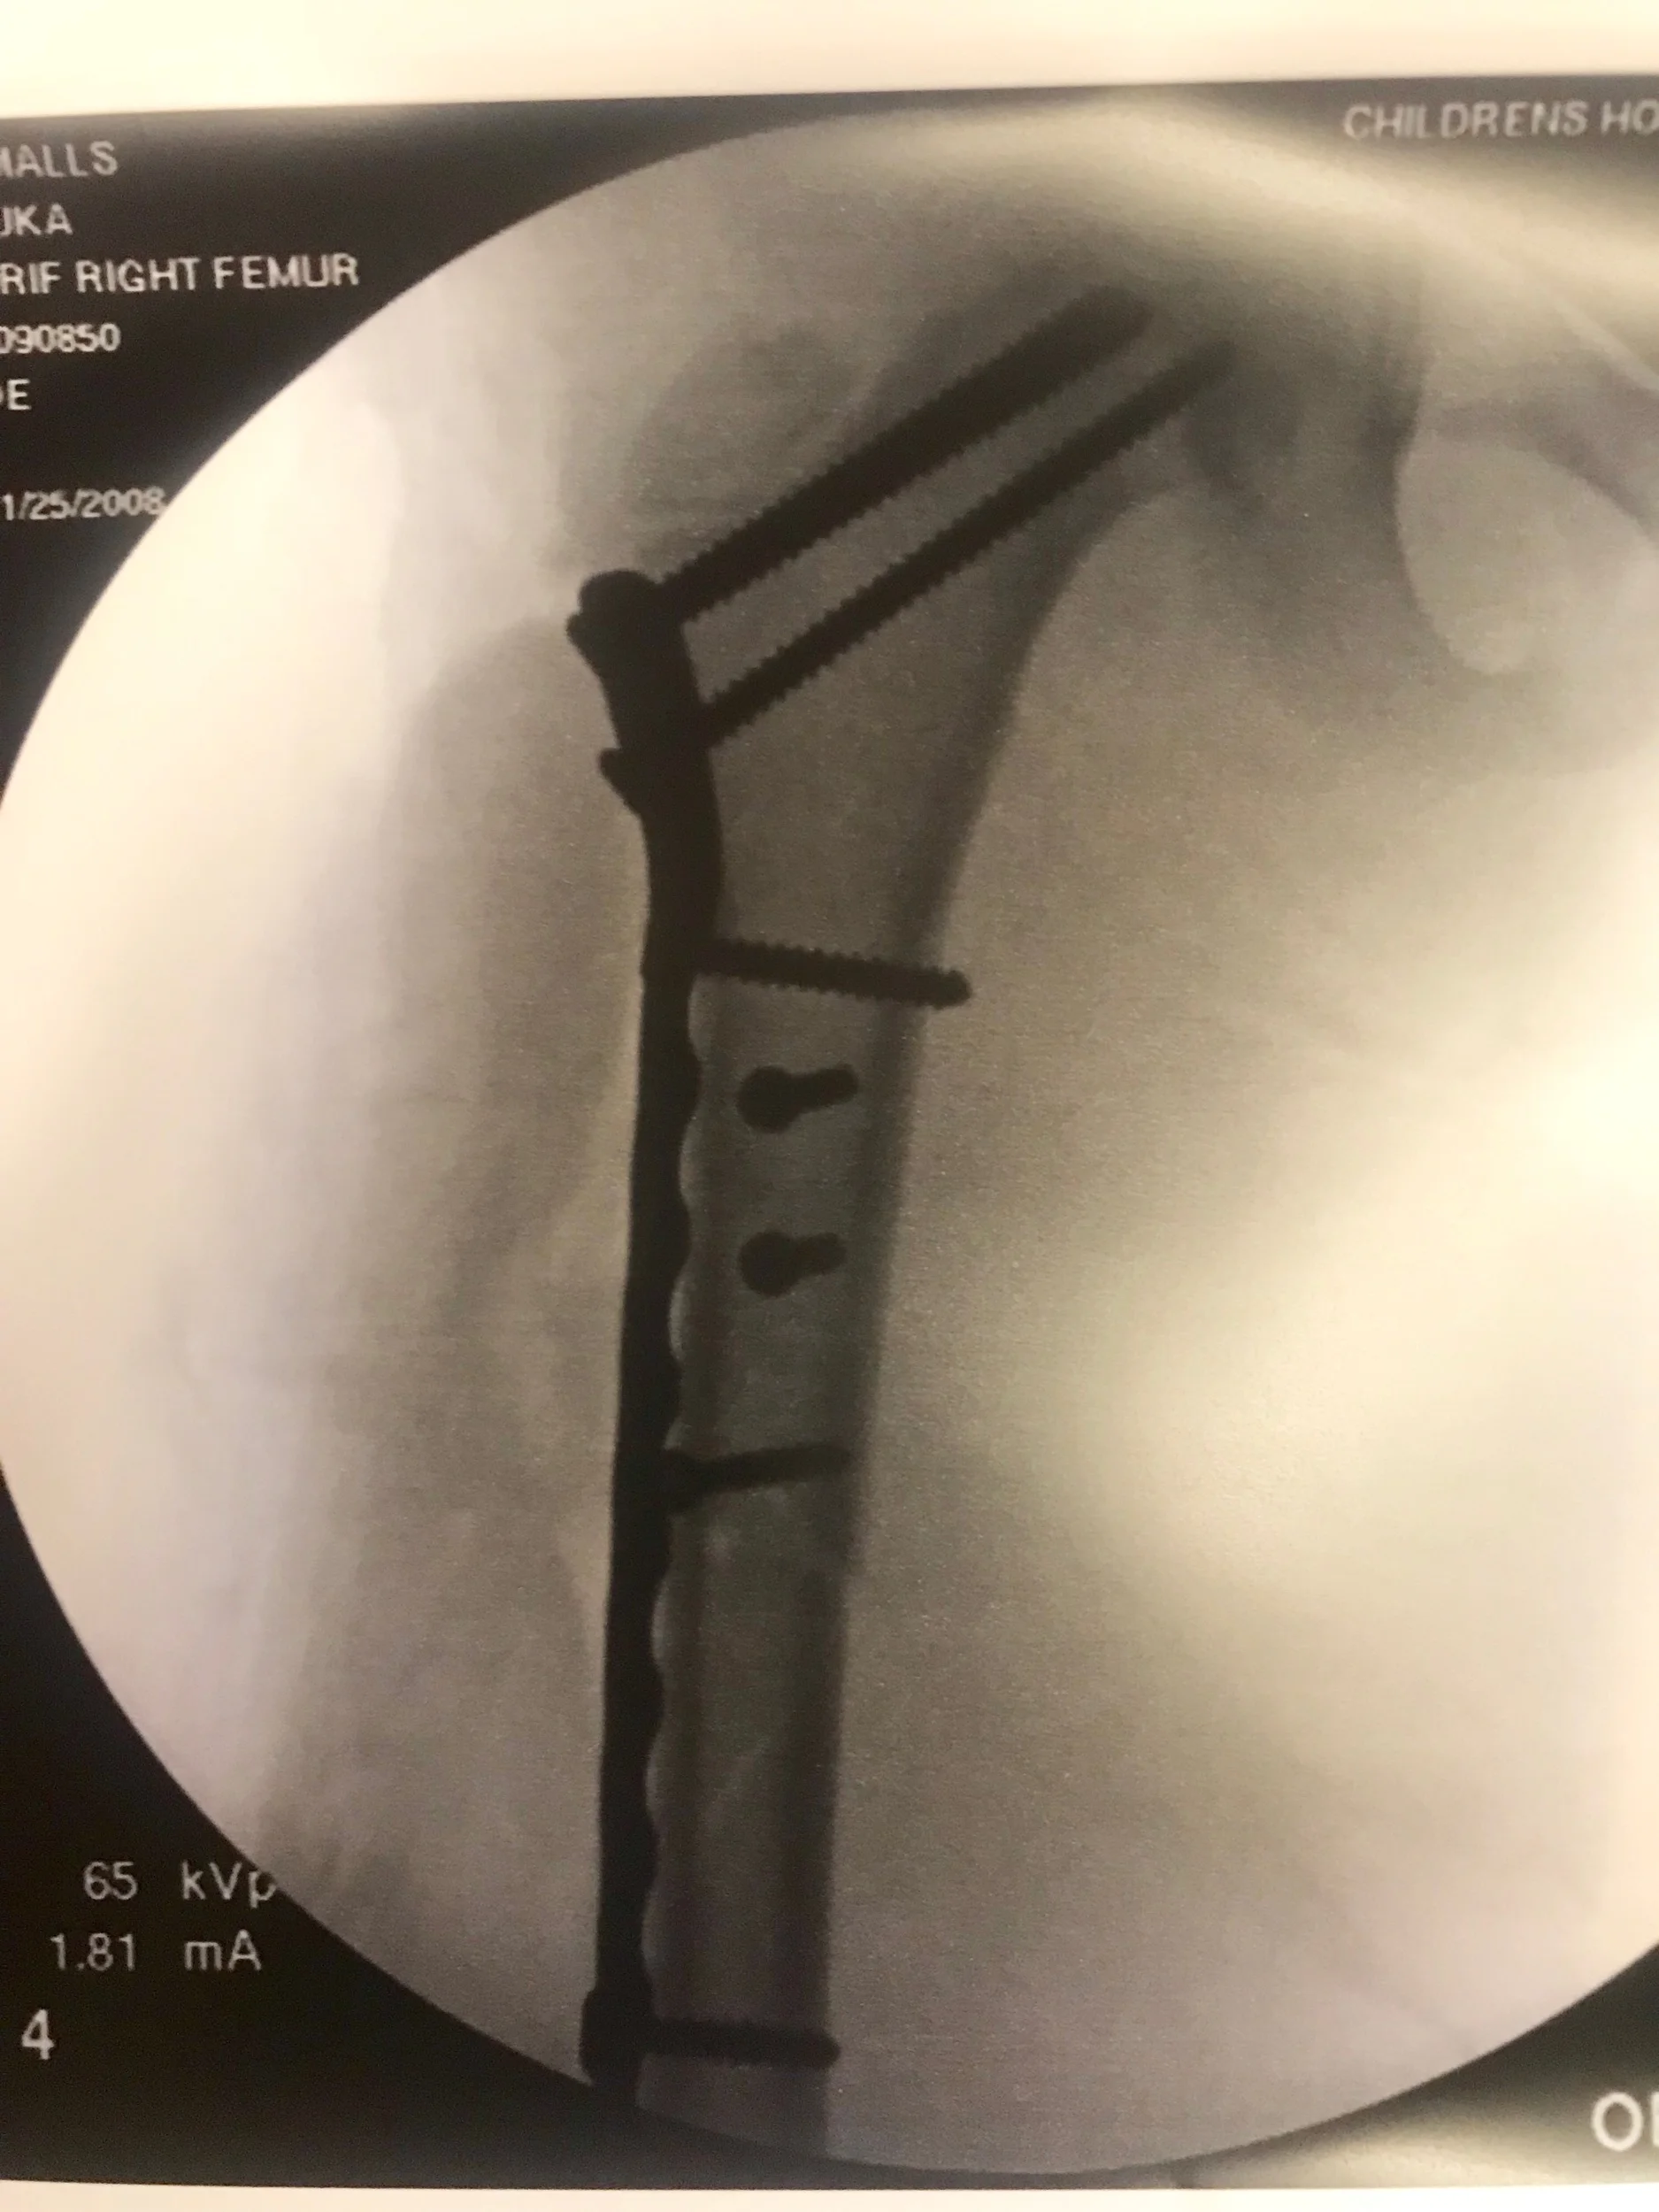

Luka broke his femur on June 20th, 2018. PAIN. Spiral fracture. 911 call that turned the shortest night of the year into a year-long adventure. Ambulance ride to Aspen ER, first drugs, decision to go to Denver, fixed wing flight for life to Children’s hospital, more PAIN as they put him in the torture device to straighten his leg, no food or drink, no sleep either, surgery mid-morning on the 21st.

Now healing. 2 months spent on crutches. Playing cards with friends. Long rehab and small successes. First pool day. Slowly back to walking, errr, limping. Soon running and then jumping. Skiing in fewer than 6months again - like nothing ever happened! Full ski racing season with ASK Branik, Maribor, Anda’s home ski club. Subsequent surgery in April to take out the metal - done by Dr. Kristan in Ljubljana hospital. Back on crutches. And back on a bike three days later. Back to full Luka-action in a month. He was ready to hit it full speed before the year was around.